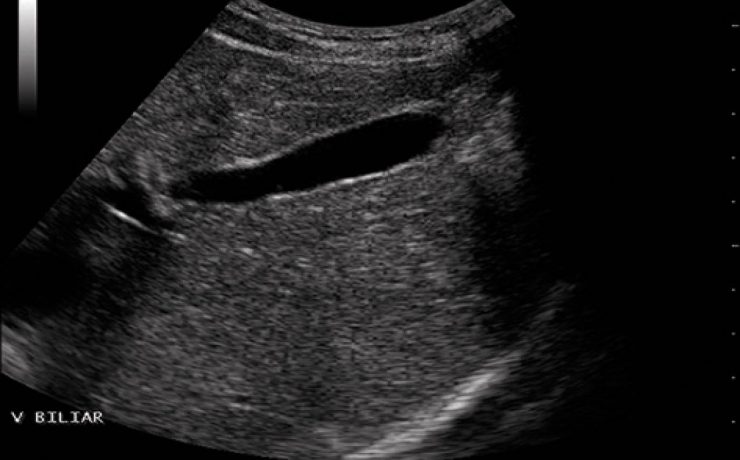

Nódulo de tiroides

La glándula tiroides es con frecuencia afectada por diferentes patologías de tipo funcional y orgánico, que conllevan a cambios funcionales y estructurales de este órgano. Cuando estos cambios son estudiados por medios radiográficos, arrojan una serie de imágenes características que contribuyen con una de las funciones médicos sociales más importantes,